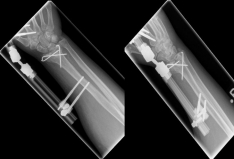

Handgelenk 4    Handgelenk 5

Pictures: In this case, the articular surface of the wrist was completely destroyed, so that only a therapy by means of outer retainer and some K-wires to correct the position was possible. Here is a practice only after removal of the outer holder after 6-8 weeks possible. Such severe joint injuries often lead to premature joint wear